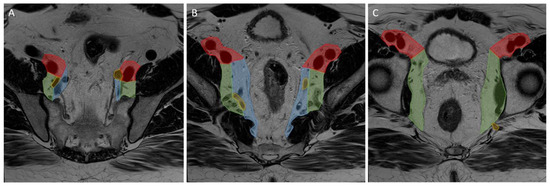

Primary and restaging MRIs of all patients were evaluated during the original studies by at least one expert radiologist in each centre. The expert radiologist in each centre was a specialized abdominal radiologist with vast experience and proven knowledge within colorectal assessment. Assessment of the LLNs was based on the largest node on the primary MRI and included the short- (SA) and long-axis (LA) diameter (measured on the transversal, coronal, or sagittal plane), the presence of malignant features (heterogeneity, border irregularity, loss of fatty centre, and shape), and anatomical location. During re-review, radiologists used a colour atlas to help determine the anatomical location of the LLN [8]. Lymphatic tissue located between the mesorectal fascia (MRF) and the lateral border of the main trunk of the internal iliac artery was considered the internal iliac compartment, and tissue ventral of the external iliac vessels was the external iliac compartment. The obturator compartment contained all lymphatic tissue lateral of the main trunk of the internal iliac artery, and once the internal iliac artery exited the pelvis, all remaining tissue was also regarded as the obturator compartment (Figure 2).

Figure 2.

Lateral lymph node compartments. Progression through a T2 transversal pelvic MRI scan from (A–C) cranial to caudal. Red: external iliac compartment, blue: internal iliac compartment, green: obturator compartment, yellow: internal iliac artery.